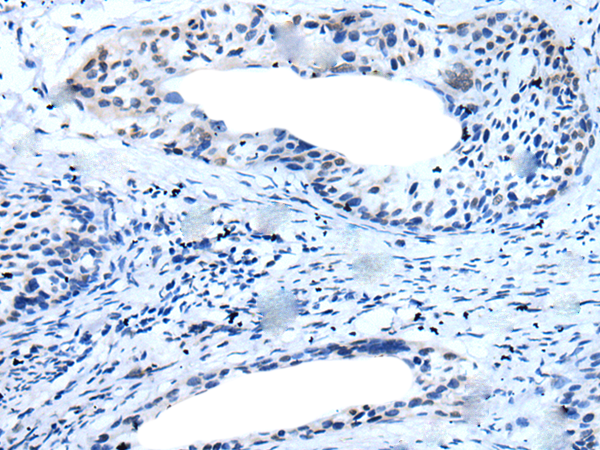

分类: 科研抗体货号: P12760别名: HHF5; CD220应用: IHC反应种属: Human, Mouse, Rat